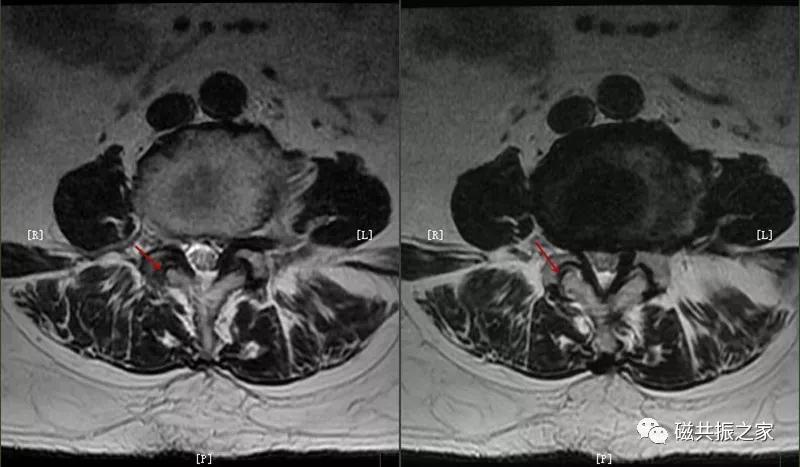

4.小关节积液

主要表现:小关节间隙液量增多,常伴随长期腰痛。